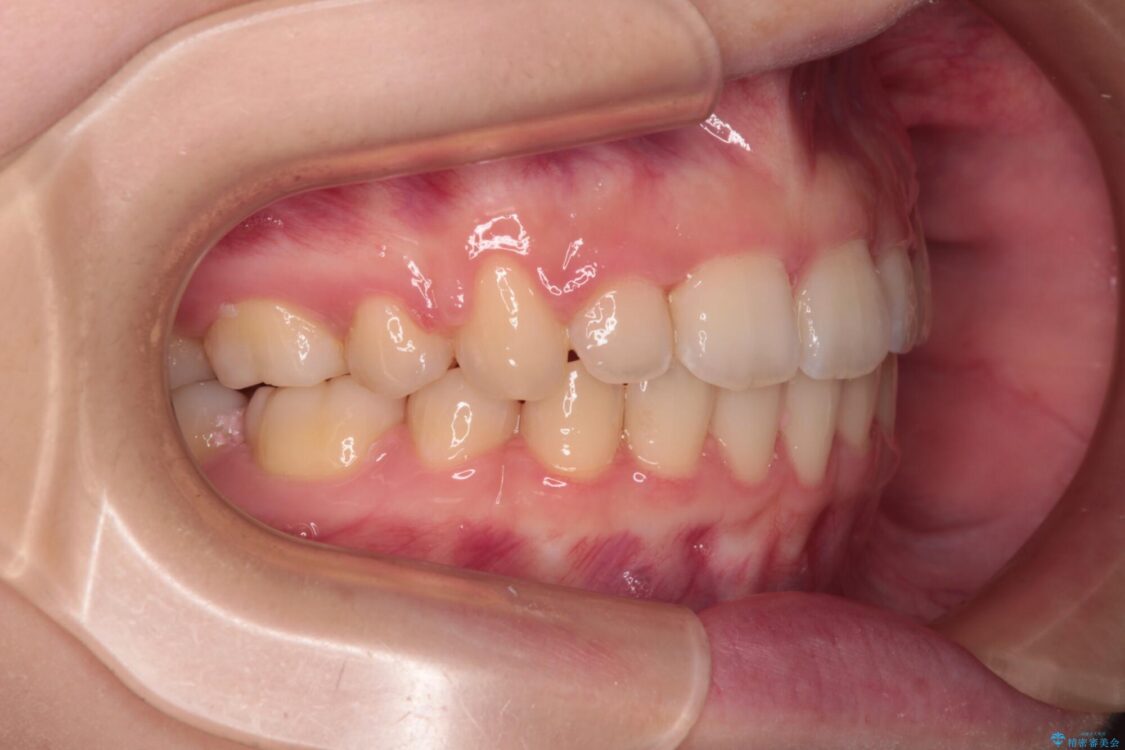

治療後

• 【モニター】口が閉じられない ワイヤー装置での抜歯矯正 治療後画像